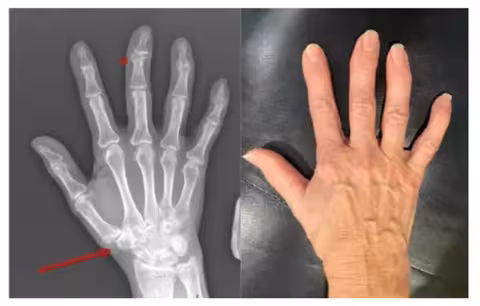

Остеоартроз розвивається поступово, і перші симптоми можуть бути майже непомітними – легка ранкова скутість, дискомфорт після фізичного навантаження або короткочасний біль у суглобах. З часом хрящова тканина втрачає еластичність, з’являється тертя, запалення й характерний «хрускіт», що заважає рухатися вільно. До ключових причин належать вікові зміни, надмірна вага, травми, спадкові фактори чи надмірні навантаження. Якщо процес прогресує, погіршується якість життя, зменшується обсяг рухів і зростає ризик деформацій.